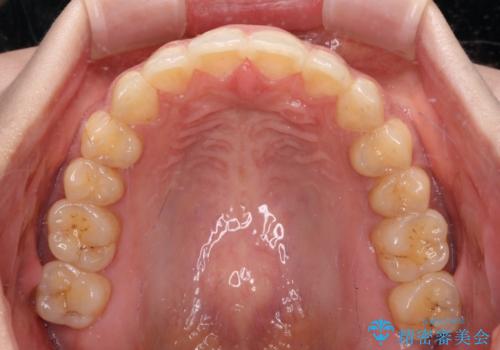

- 前歯のデコボコと上下前歯の隙間を気にして来院された患者様です。

下顎前歯はデコボコのため、歯肉が腫れやすくなっていました。

また、舌突出癖のため、上下前歯の間に隙間ができてしまい、上顎前歯が前方に傾斜している状態でした。

舌突出癖改善のためのトレーニングを行いながら、インビザラインにて矯正治療を行うこととしました。